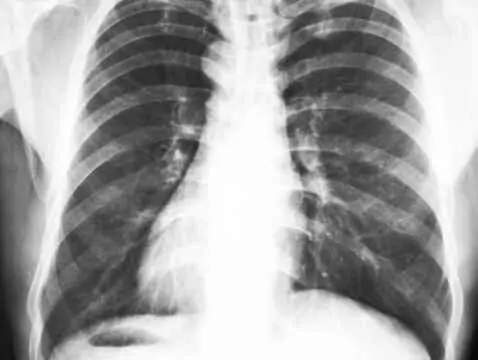

Do rozpoznawania chorób układu krążenia, a szczególnie wad serca, które są największym problemem w kardiologii, służy dobrze zebrany wywiad, badanie fizykalne oraz szereg badań...

Wady wrodzone serca występują u 7-8 na 1000 żywo urodzonych noworodków i są przyczyną około 20% wszystkich zgonów w tej grupie dzieci. W większości przypadków przyczyna powstania wady serca pozostaje...